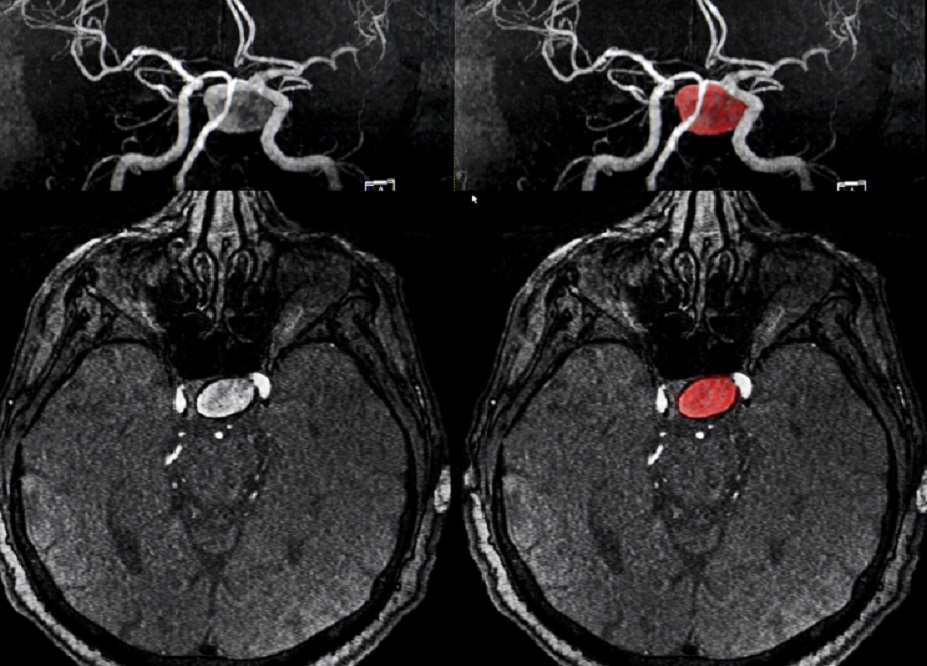

脑动脉瘤诊断

一旦决定排除aSAH,病人应该接受一个完整的评估。首先是突发的头部非对比计算机断层扫描,如果在头痛/症状出现的前6小时内进行,其灵敏度接近全切。其灵敏度随时间急剧下降,分别在5、7和14天达到85%、50%和30%。反之,腰椎穿刺的产量随时间增加。事实上,当从症状出现的12小时至14天进行腰椎穿刺时,SAH的阴性评估值为全切。黄色素沉着症的诊断结果是黄色脑脊液,是溶解的红细胞血红蛋白氧化的结果。这种氧化反应需要12小时,这是因为超过这段时间后它的灵敏度很高[33].在较初的12小时后黄色色素的缺乏排除了SAH 。头部计算机断层扫描和脑脊液分光光度分析是诊断SAH的金标准。

目前,磁共振成像作为可能出现SAH的患者的研究选择是不切实际的,因为它需要更长的时间来进行,并且幽闭恐惧症患者的耐受性差。然而,磁共振成像可用于初始检查不明确或不明确的情况。例如,如果磁共振成像在GRE和FLAIR上没有显示异常信号,因创伤性叩击而在脑脊液中有红细胞的头部CT为阴性的患者可以避免侵入性脑血管造影。此外,可以同时进行磁共振血管成像来评估任何动脉瘤,因为这些动脉瘤破裂的可能性更高。正常的MRA将提供排除SAH的进一步证据。